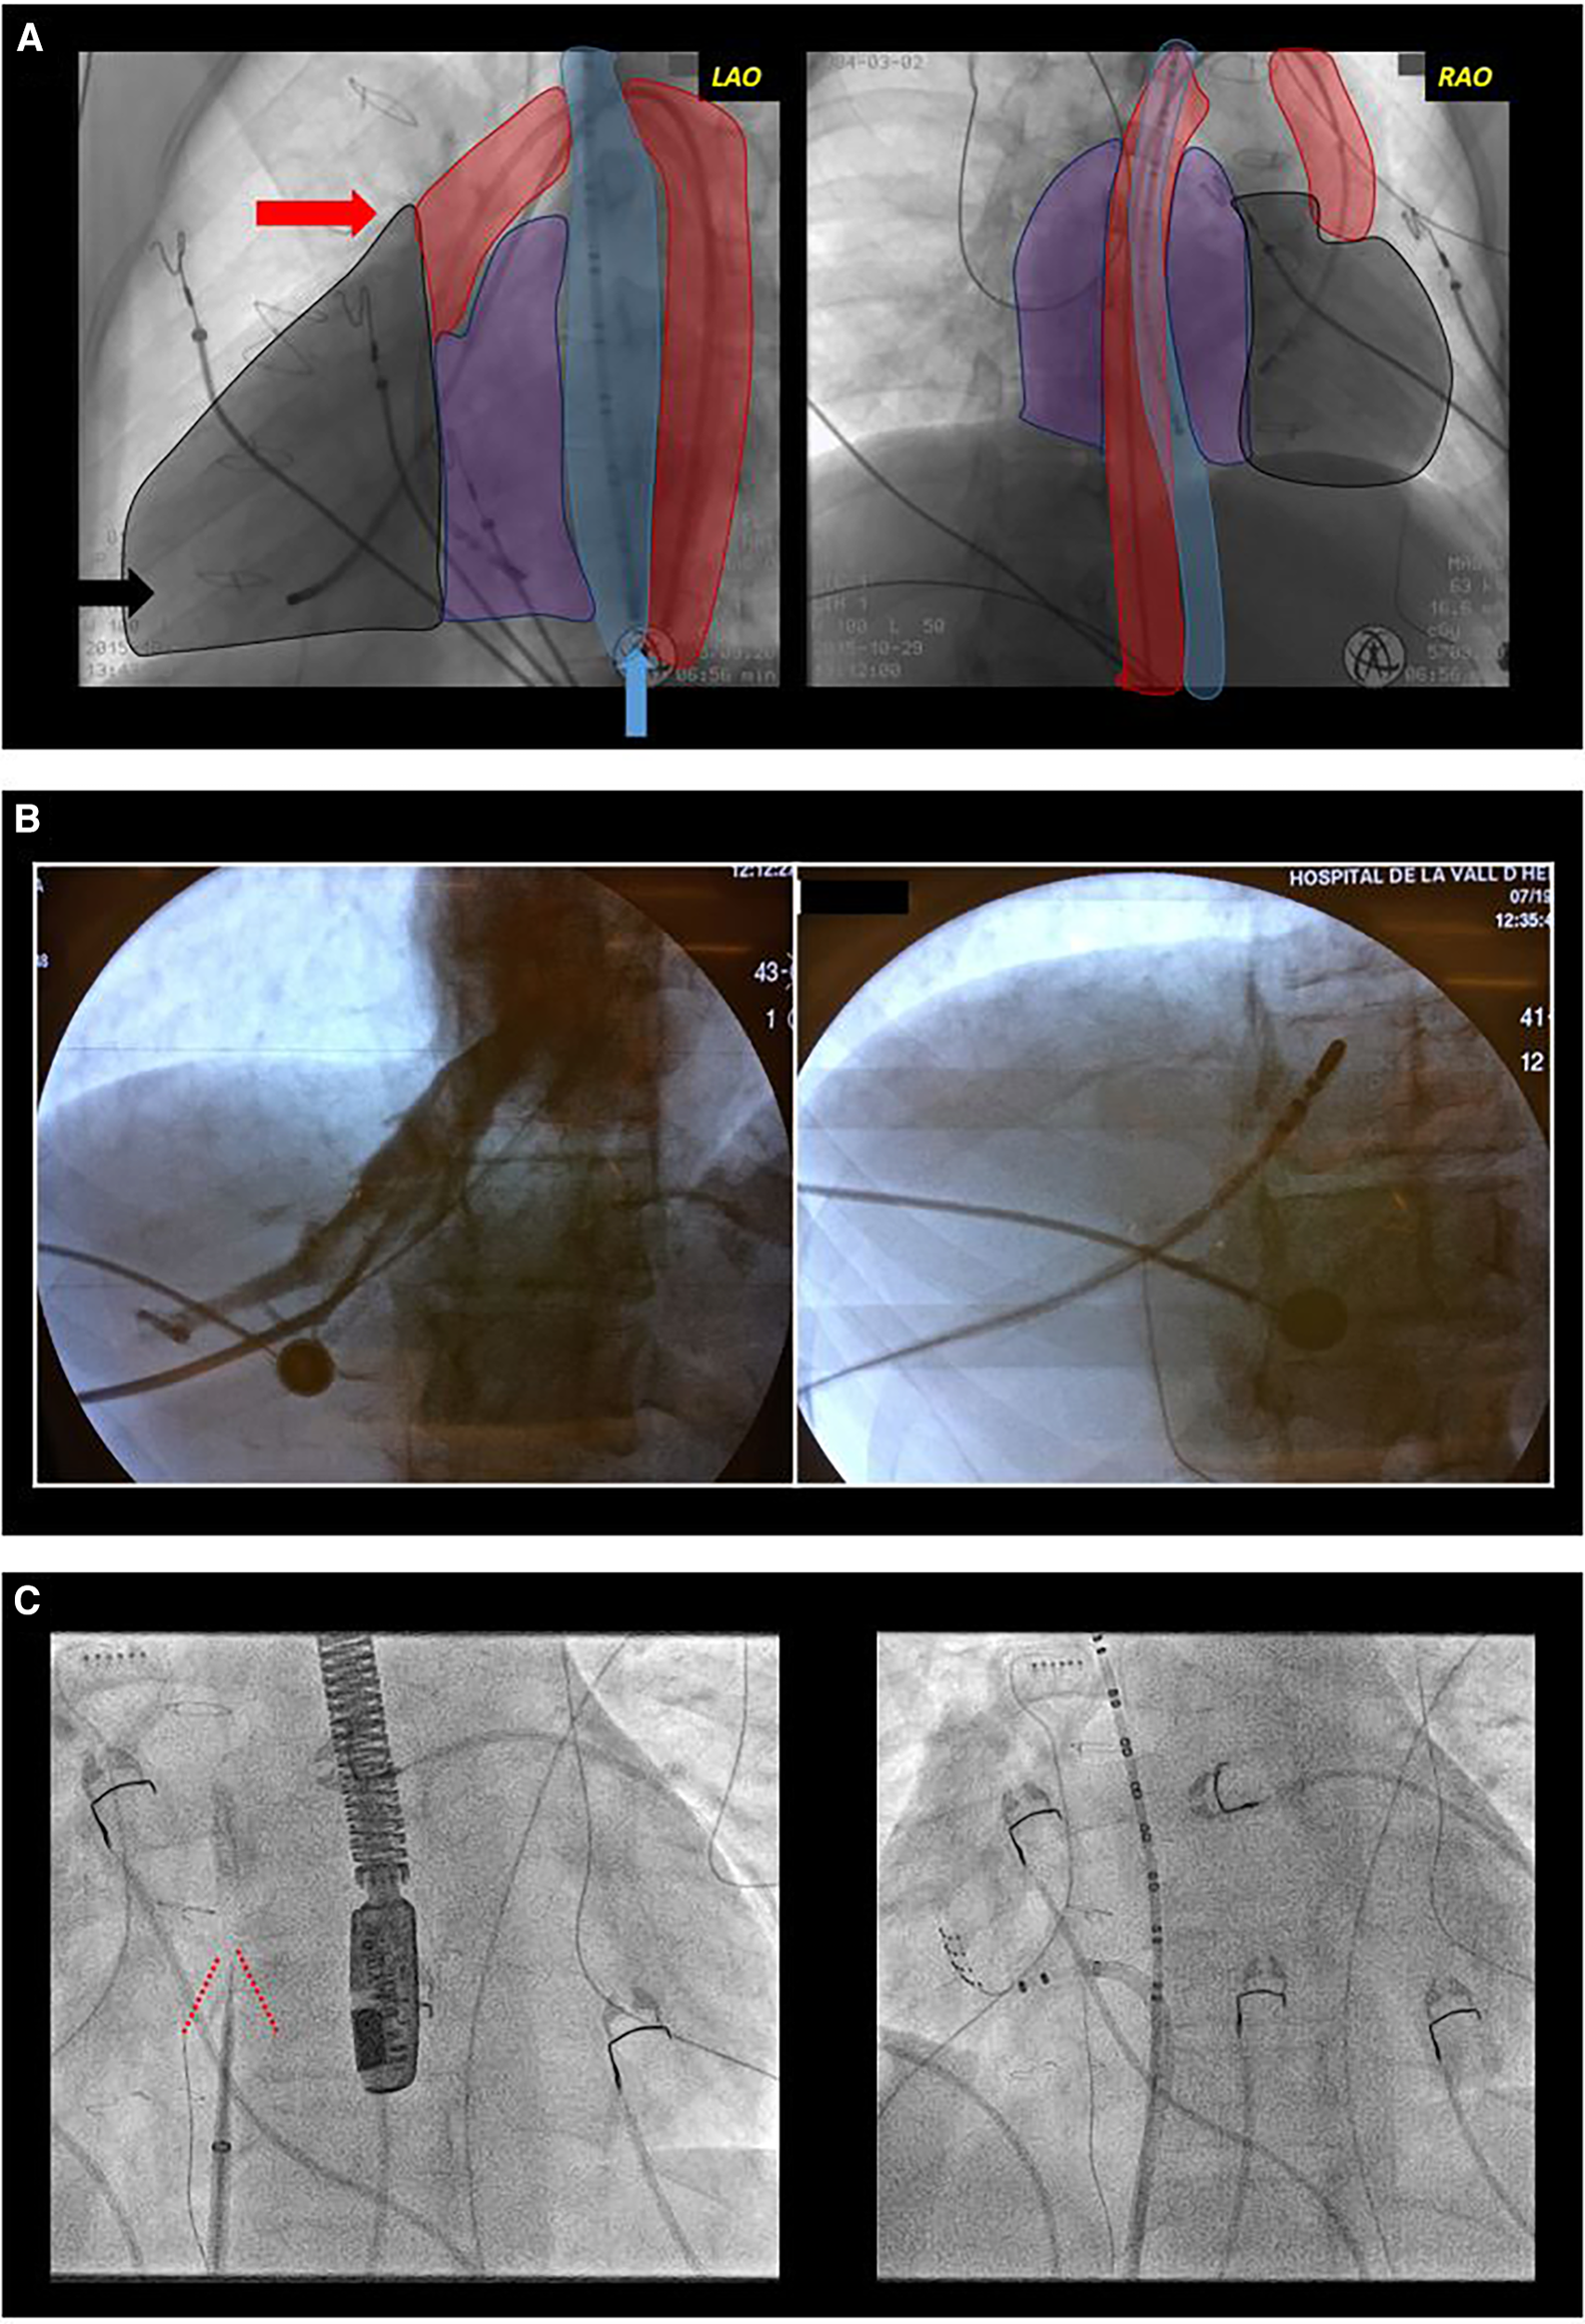

Figure 2

Difficult access. (A) Complex congenital heart disease with a single ventricle type, mesocardia, and dextroapex, initially repaired with classic Fontan surgery which was later converted to Fontan with intracardiac tube. Electrophysiological study was performed due to syncopal supraventricular tachycardia. Conventional radiological projections are shown: left anterior oblique (LAO, left image) and right anterior oblique (RAO, right image). The outlines of the esophagus (blue), aorta (red), ventricle (black), and atria (purple) are shaded. Due to the absence of femoral venous access, a transesophageal diagnostic catheter (blue arrow) was introduced for atrial sensing, and through the femoral artery, a tetrapolar catheter to the ventricle (black arrow) for rescue ventricular stimulation and a mapping-ablation catheter for treatment (red arrow) were progressed. (B) Transhepatic access guided by fluoroscopy. In the first fluoroscopy image, contrast injection into the hepatic venous system can be observed. In the second image, the catheter is progressed through this venous system. (C) Transeptal access in a patient with transposition of the great arteries corrected with atrial switch surgery (Senning). Both fluoroscopy images show an left anterior oblique projection. In the left image, a transeptal puncture needle oriented anteriorly and towards the right shoulder. Tenting of the interatrial baffle is observed (red lines). In the right image, a mapping-ablation catheter has been advanced through a long sheath to the neo-pulmonary venous atria.